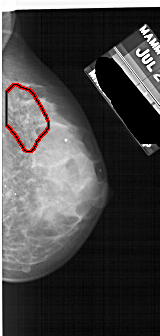

A_1734_1.LEFT_CC

LEFT_CC LINES 4936 PIXELS_PER_LINE 2296 BITS_PER_PIXEL 12 RESOLUTION 43.5 NON_OVERLAY

FILE: A_1734_1.RIGHT_CC.OVERLAY

TOTAL_ABNORMALITIES 1

ABNORMALITY 1

LESION_TYPE CALCIFICATION TYPE PLEOMORPHIC DISTRIBUTION SEGMENTAL

ASSESSMENT 4

SUBTLETY 3

PATHOLOGY BENIGN

TOTAL_OUTLINES 1

BOUNDARY